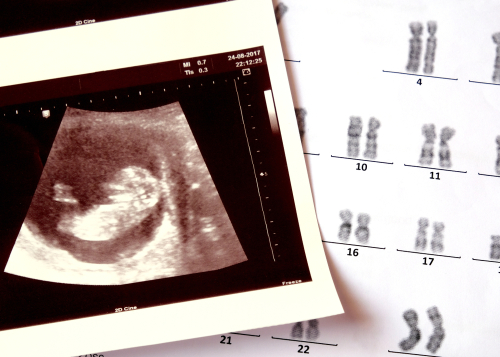

【産婦人科医監修】エコー写真の見方を妊娠初期から解説!向き・性別の見分け方は?ダウン症や子宮筋腫もわかる?

エコー写真にはさまざまな情報が詰まっているため、見方や向きを覚えておくと赤ちゃんの成長の様子がしっかりと確認できます。妊娠週数や計測した数値をあらわすアルファベットの用語の意味、胎児の成長に合わせた妊娠週数ごとの写真の見え方、エコー検査でわかることを産婦人科医監修で解説していきます。

エコー写真でダウン症はわかる?

エコー写真では首の後ろがむくんでいたり、鼻が低かったりといった特徴が見られることがあります。こういった特徴はダウン症の所見と重なる部分がありますが、エコー検査ではダウン症の確定診断はできません。

ダウン症と確定するためには、さらに詳細な検査が必要です。また、ダウン症と重なる特徴が見られたとしても、必ずしもダウン症とは限りません。定期的に健診を受け、継続した観察を行うようにしましょう。